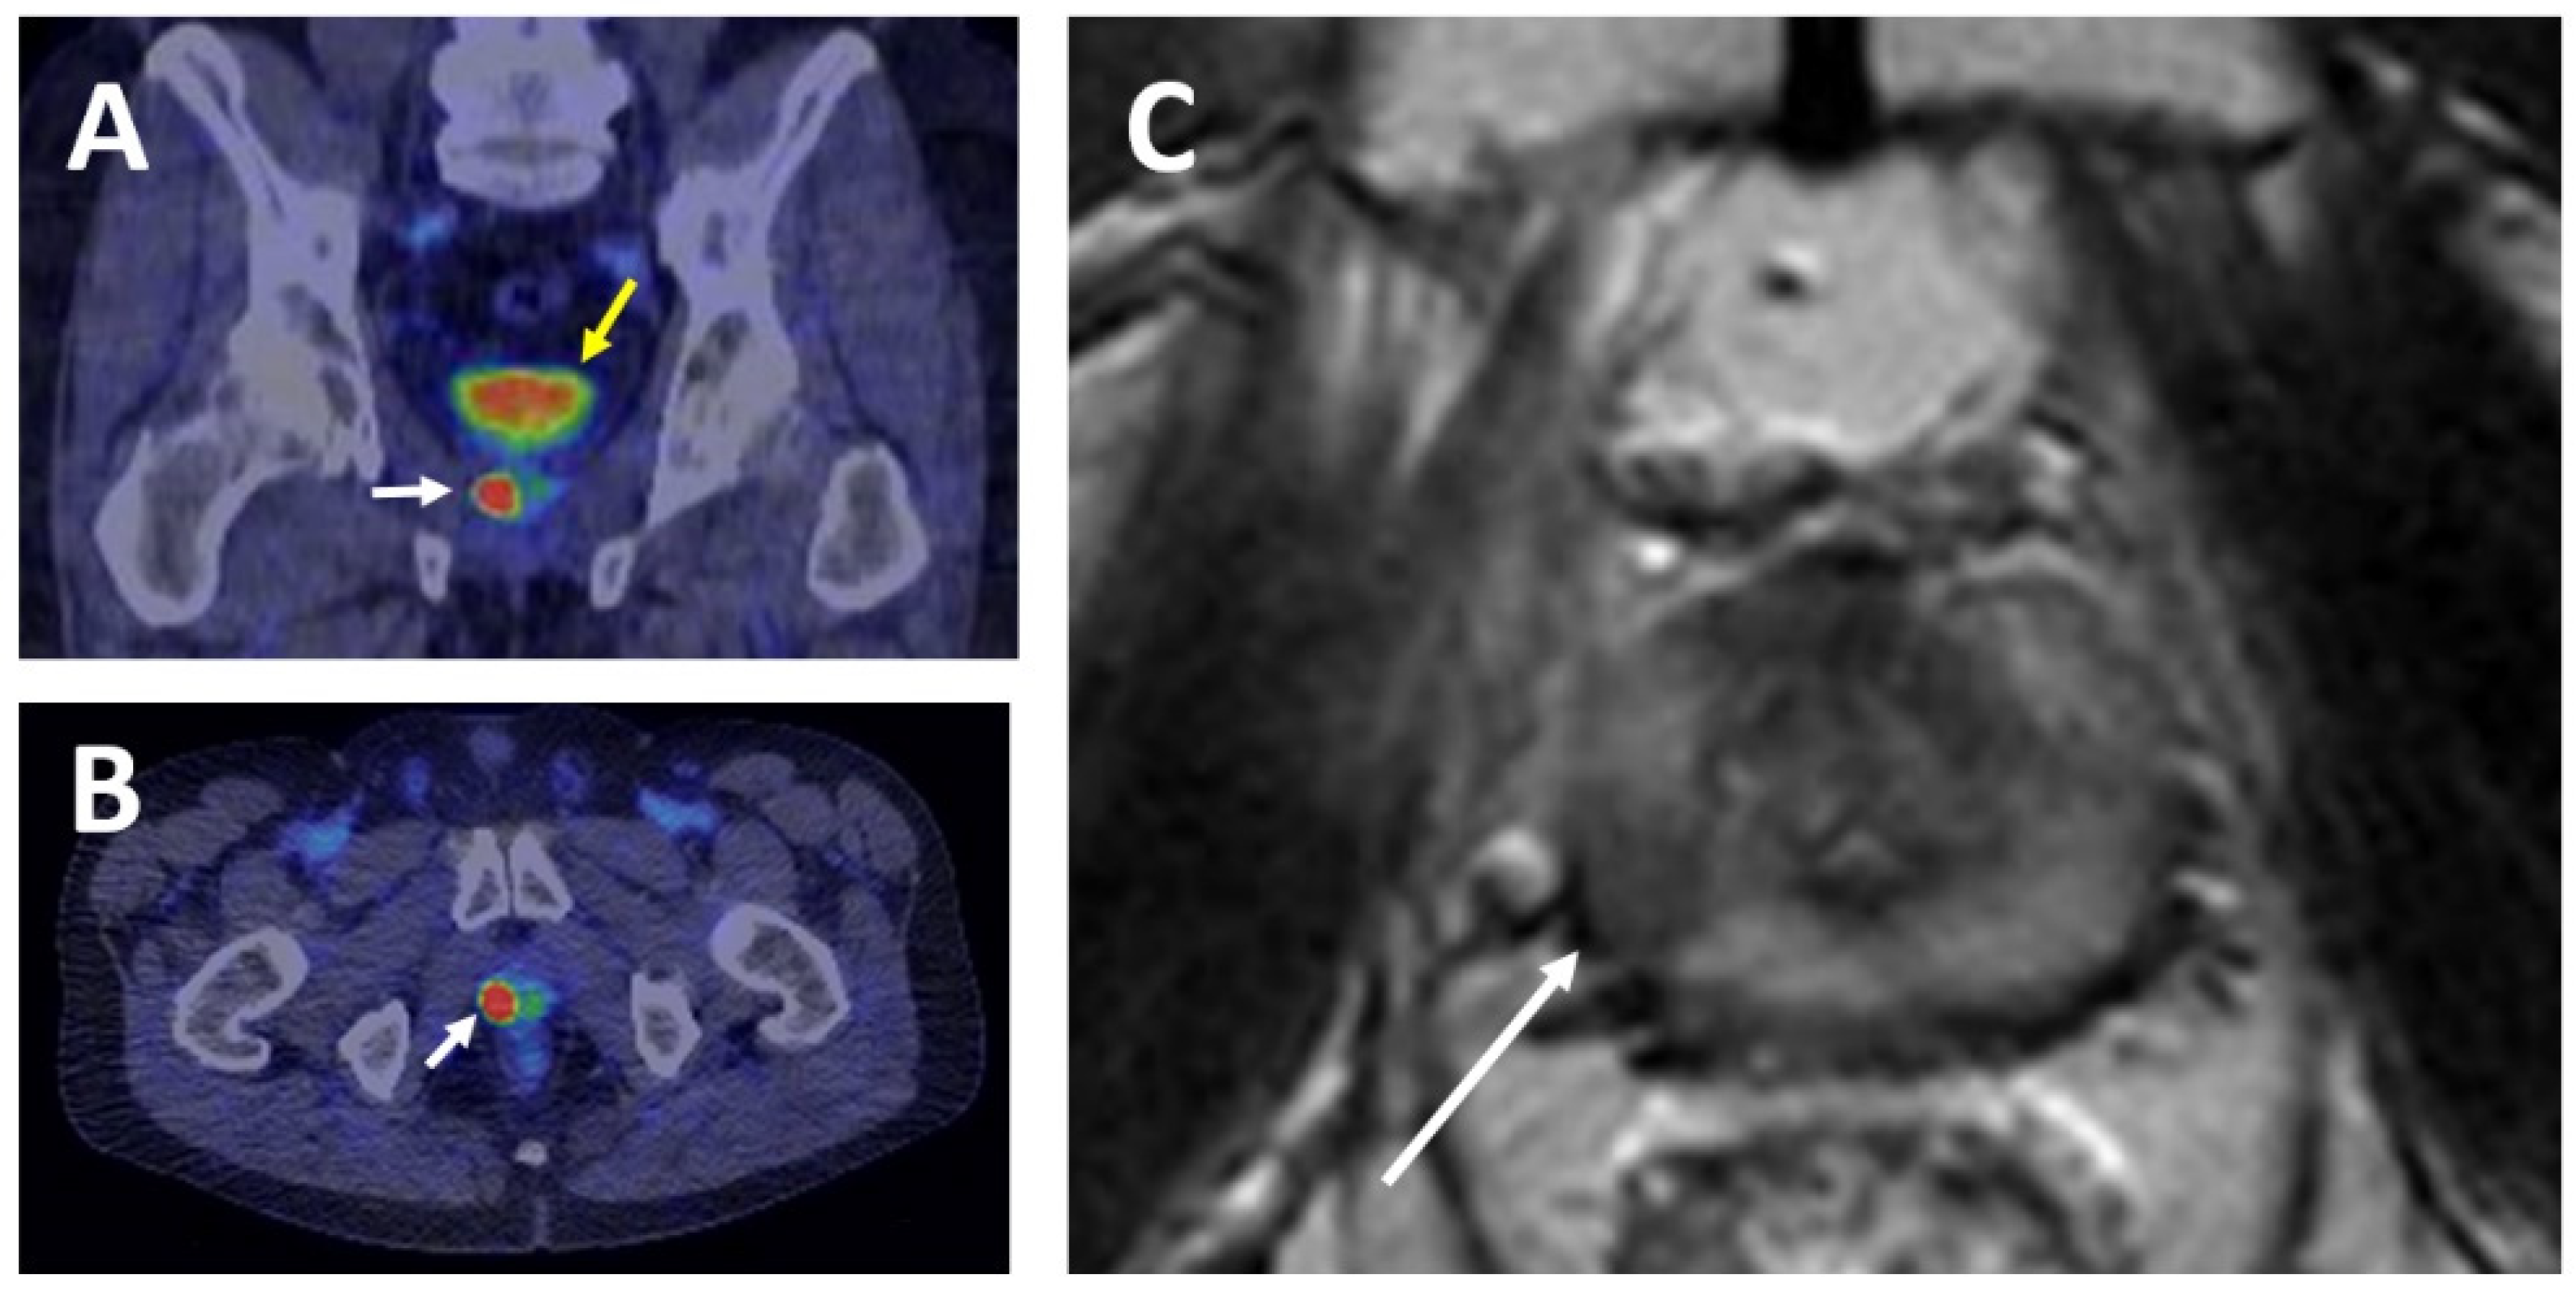

- Kähkönen, E.; Jambor, I.; Kemppainen, J.; Lehtiö, K.; Grönroos, T.J.; Kuisma, A.; Luoto, P.; Sipilä, H.J.; Tolvanen, T.; Alanen, K.; et al. In Vivo Imaging of Prostate Cancer Using [68Ga]-Labeled Bombesin Analog BAY86-7548. Clin. Cancer Res. 2013, 19, 5434–5443. [Google Scholar] [CrossRef] [PubMed]

- Minamimoto, R.; Sonni, I.; Hancock, S.; Vasanawala, S.; Loening, A.; Gambhir, S.S.; Iagaru, A. Prospective Evaluation of 68Ga-RM2 PET/MRI in Patients with Biochemical Recurrence of Prostate Cancer and Negative Findings on Conventional Imaging. J. Nucl. Med. 2018, 59, 803–808. [Google Scholar] [CrossRef]

- Fassbender, T.F.; Schiller, F.; Mix, M.; Maecke, H.R.; Kiefer, S.; Drendel, V.; Meyer, P.T.; Jilg, C.A. Accuracy of [68Ga]Ga-RM2-PET/CT for diagnosis of primary prostate cancer compared to histopathology. Nucl. Med. Biol. 2019, 70, 32–38. [Google Scholar] [CrossRef]

- Hoberück, S.; Michler, E.; Wunderlich, G.; Löck, S.; Hölscher, T.; Froehner, M.; Braune, A.; Ivan, P.; Seppelt, D.; Zöphel, K.; et al. 68Ga-RM2 PET in PSMA- positive and -negative prostate cancer patients. Nuklearmedizin 2019, 58, 352–362. [Google Scholar] [CrossRef] [PubMed]